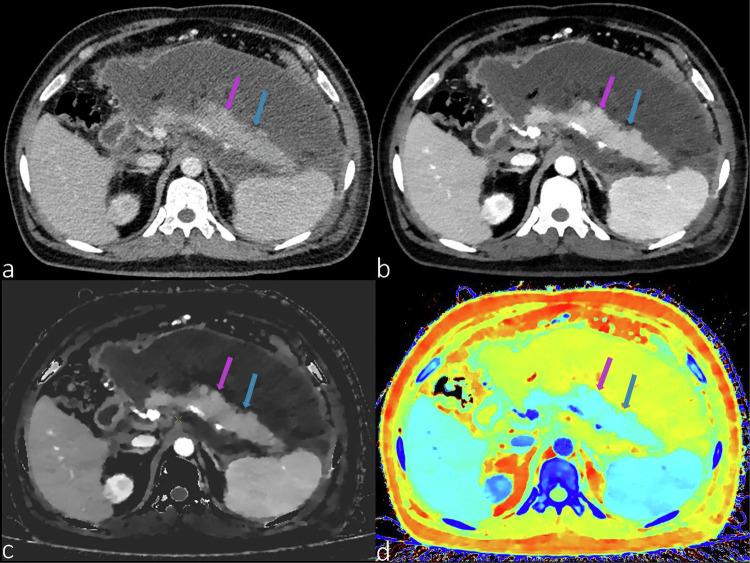

DLCT consists of a top layer sensitive to lower-energy photons and a bottom layer sensitive to higher-energy photons. This configuration enables simultaneous acquisition of two energy spectra from a single X-ray beam ensuring consistent spatial alignment and temporal resolution. Spectral raw images allow image post-processing to improve image quality, reduce radiation doses and contrast media doses, and generate multiple quantitative parameters. It has broad potential for early detection, accurate staging, efficacy assessment, and prognosis prediction of liver, pancreatic, and gastrointestinal diseases, as well as for the assessment of digestive system vasculature.

DLCT由对低能光子敏感的顶层和对高能光子敏感的底层组成。这种配置能够从单个X射线束同时采集两个能谱,确保空间对准和时间分辨率一致。光谱原始图像允许进行图像后处理,以提高图像质量、降低辐射剂量和造影剂剂量,并生成多个定量参数。它在肝脏、胰腺和胃肠道疾病的早期检测、准确分期、疗效评估和预后预测以及消化系统血管评估方面具有广阔的潜力。